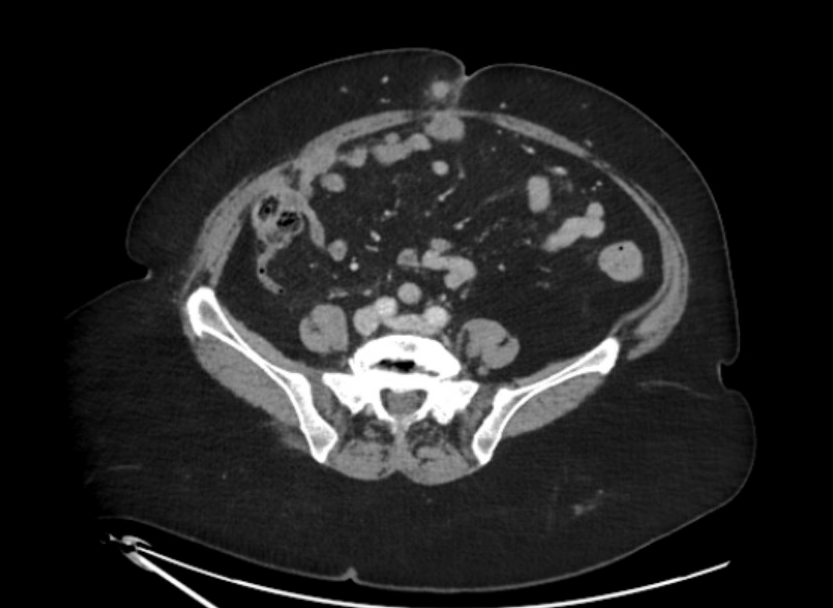

Ecografía reglada de partes blandas: Nódulos subcutáneos e intrabdominales sospechosos de malignidad. La tomografía abdominal describe múltiples implantes sólidos peritoneales y en pared abdominal, compatibles con metástasis.

Nódulo de Hermana María José, correspondiente a metástasis umbilicales de carcinoma de endometrio, con carcinomatosis peritoneal. Diagnóstico diferencial con lipoma, quiste sebáceo, fibroma.

El Comité multidisciplinar de tumores decide Biopsia guiada por ecografía + PET/TC que confirma múltiples implantes hipermetabólicos. Biopsia: Carcinoma de endometrio con pérdida de expresión de PMS2 y MLH1, confirmando la naturaleza metastásica del nódulo umbilical. Tratamiento con citoreducción e Inmunoterapia.